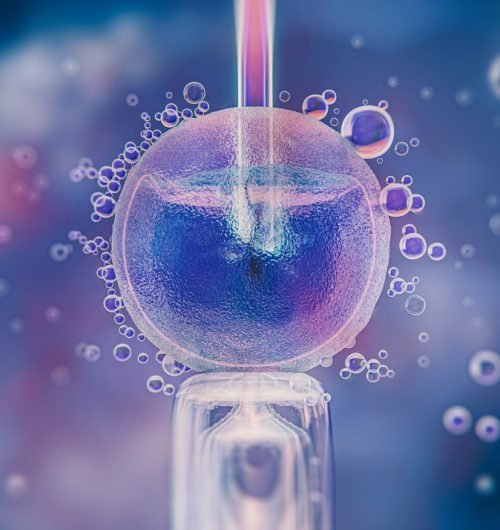

What is IVF (In Vitro Fertilization) ?

IVF, or In Vitro Fertilization, is an advanced fertility treatment where eggs and sperm are combined in a lab to create an embryo, which is then placed in the uterus to achieve pregnancy. At Pramukh IVF Center, we make this process safe, effective, and caring – helping couples turn their dream of parenthood into reality.

IVF is a medical process where eggs are collected from the woman and fertilized with sperm in a laboratory. The developed embryos are then transferred into the uterus to achieve pregnancy. The treatment involves steps like consultation, ovarian stimulation, egg retrieval, fertilization, and embryo transfer. With advanced technology and skilled specialists, IVF in Ahmedabad has become a safe and effective option for couples facing fertility challenges.

A semen sample is provided (or thawed, if frozen). The lab processes it to select the healthiest, most motile sperm. - Fertilization (IVF or ICSI)

Eggs and sperm are combined in the lab. With ICSI, a single sperm is injected into each mature egg to assist fertilization. - Embryo Culture (3–5 days)